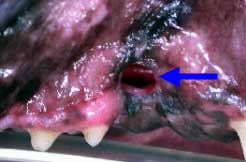

Blue arrow: perio-endo lesionWhite arrow: note immature pulp cavity indicating tooth death at younger age

Dilacerated and nonvital mandibular carnassial tooth with stage 4 periodontal lesion